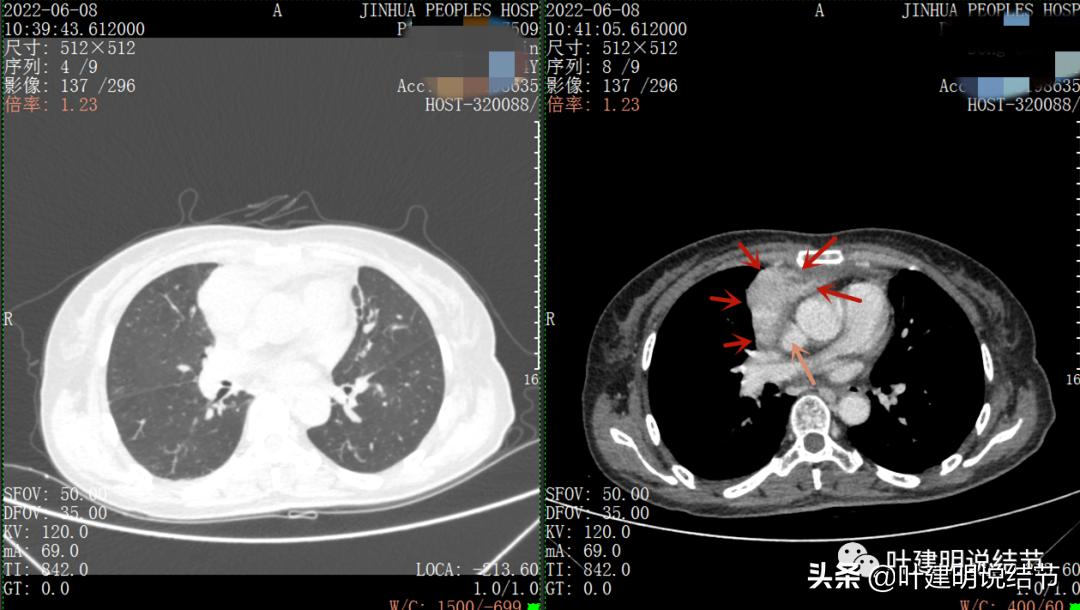

再来看看她的CT增强图像:

以下图片左侧是肺窗,右侧是纵隔窗。红色箭头示病灶,桔色箭头示无名静脉,黄色箭头示支气管,砖色箭头示上腔静脉,蓝色箭头示主动脉,紫色箭头示肺动脉。

病灶胸顶较高位置就出现了,在无名静脉水平

无名静脉略受压